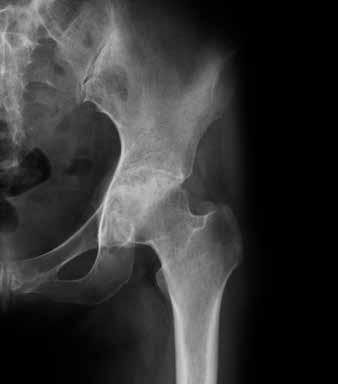

Articulation de hanche saine

Le diagnostic

Pour le diagnostic de l’arthrose, le ou la médecin procède à une anamnèse et à un examen physique et exclut la possibilité que les symptômes soient attribuables à une autre maladie. Les radiographies permettront en outre de déterminer le degré d’évolution et la gravité de l’arthrose. Contrairement à ce qui est le cas pour la polyarthrite

Articulation de hanche arthrosique

rhumatoïde, l’examen sanguin ne joue qu’un rôle secondaire dans le diagnostic de l’arthrose. Il est surtout demandé en cas de carences ou de troubles du métabolisme.

La réponse à cette question est difficile avec une évolution éminemment variable d’une personne à l’autre. L’arthrose peut toucher une comme plusieurs articulations. Il est impossible dans un premier temps de dire si une personne va devoir affronter des douleurs, des raideurs ou une perte de mobilité. Il arrive que les radiographies montrent des modifications importantes sans que la personne atteinte ne perçoive quoi que ce soit au quotidien. À l’inverse, les douleurs ressenties peuvent être vives alors que la dégénérescence du cartilage constatée sur les radios reste limitée.